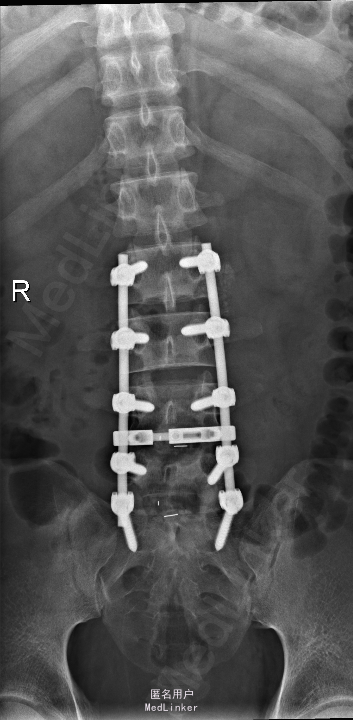

诊断:腰椎间盘突出症并椎管狭窄 处理: 1、完善相关辅助检查,明确诊断,有无手术指证; 2、完善手术评估,有无手术禁忌,手术风险及并发症; 3、在全麻下行腰椎后路多节段减压椎间植骨融合内固定术 4、腰2-3,腰3-4行开窗减压,腰4-5,腰5-骶1行椎间Cage植骨融合

随访: 1、应常规术后1个月、3个月、半年随访; 2、术后患者腰痛较前减轻,下肢麻木感觉较前好转,下肢活动较前有力,屈髋、伸膝、踝背伸肌肌力左侧4级,右侧4-5级,踇背伸、跖屈肌力左侧4级+,右侧4-5级,左侧肢体抬高试验阴性。 讨论: 1、多节段腰椎间盘突出,手术指证把握 2、责任节段的确立,以影像学间盘突出节段为依据,以影像学与临床表现确立责任节段间盘为依据,还是术中探查为金标准? 3、多节段间盘突出,开窗髓核VS椎间植骨融合? 4、开窗髓核与椎间植骨融合相结合,如何确定融合节段与开窗节段? 5、多节段内固定,腰椎活动度影响,稳定与腰椎活动功能的平衡?